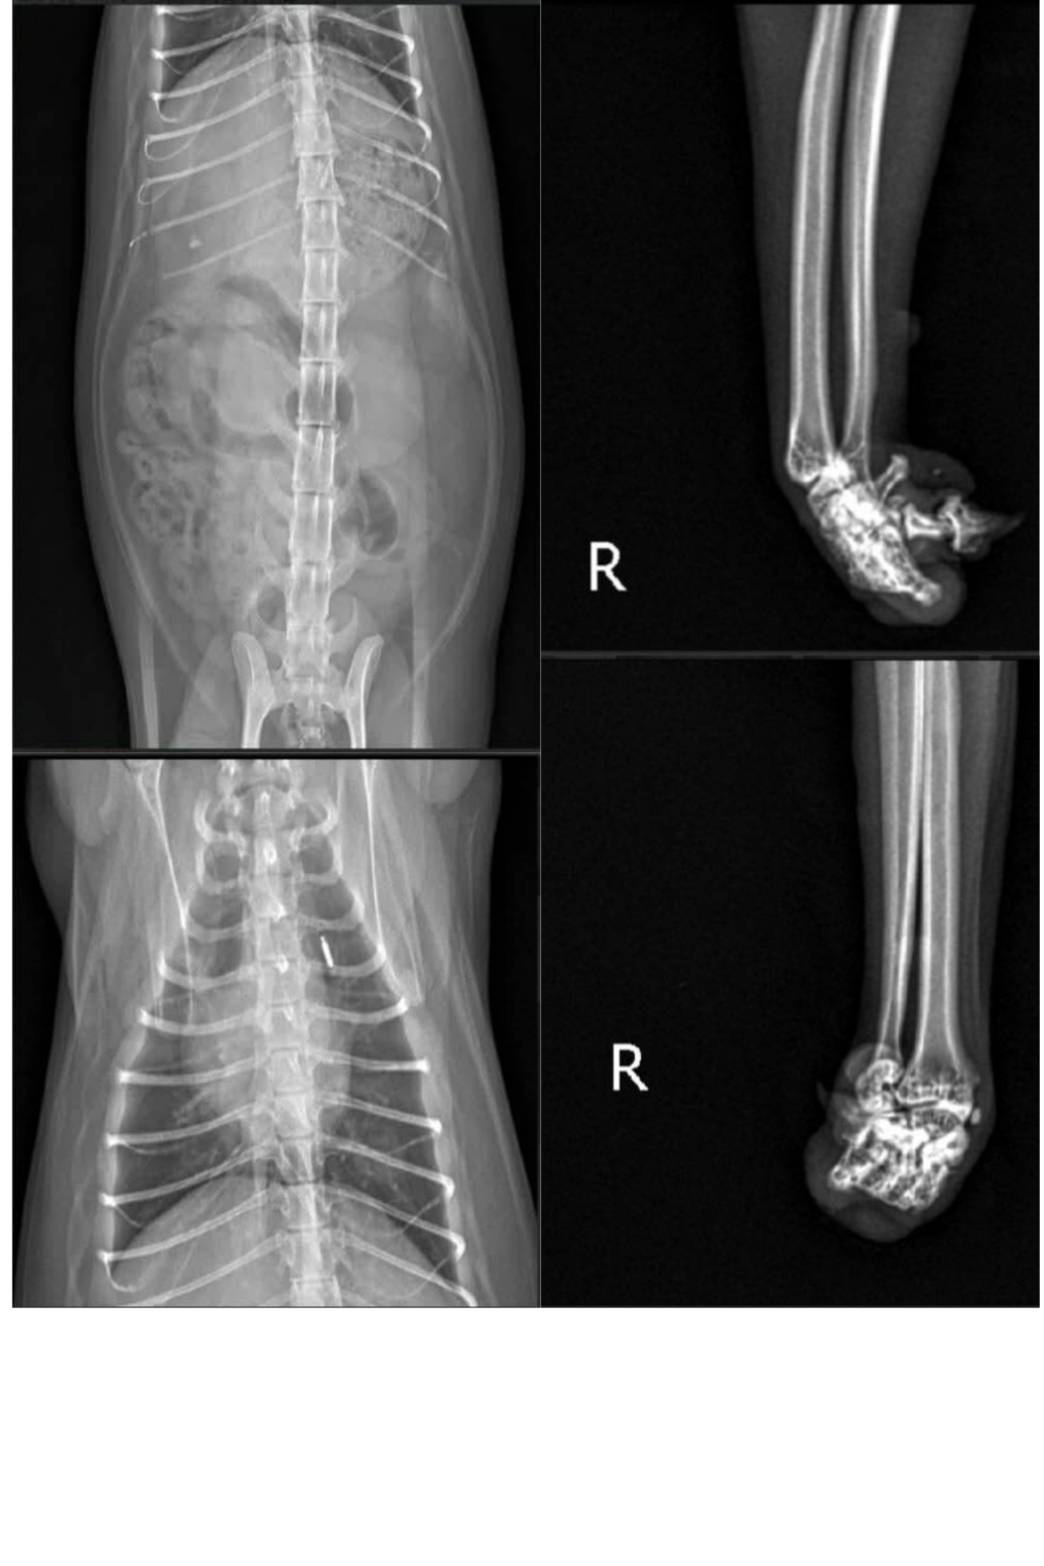

主題: 腳趾先天發育異常的Sabi 申請者姓名: TNR協會 花色: 玳瑁 申請日期: 2026-04-15 12:13:45 申請者部落格: https://www.facebook.com/SupportTNR/?locale=zh_TW 申請者臉書網址: https://www.facebook.com/SupportTNR/?locale=zh_TW 所在縣市/合作醫院: 台北市/沐恩動物醫院 治療費用: 10500元 需求名額: 35人 平均每單位: 300元 已報名名額: 0 尚需求名額: 35 報名人員: 候補人員: 因考慮無人遞補、轉匯收費、信用卡刷卡匯率、寄送收據與郵資等成本,每筆醫助人數將斟酌彈性增加1-5位名額。 動物病情說明: Sabi是台北烏來一位原住民愛媽餵養照顧的親人玳瑁貓,於2026年4月愛媽發現Sabi走路有些歪斜,且因該餵養地區常設有捕獸夾,同時偶有不友善的登山客會驅打浪貓,愛媽在不忍下發文送養,希望能有善心人士收養Sabi,幸運的是,一位高雄愛媽在看到貼文後表示願意領養照顧,於是烏來愛媽嘗試誘捕Sabi,但無奈一直能未順利,因此聯繫上協會希望協助誘捕,於是協會義工於2026年4月13日前往烏來進行誘捕,很快地就Sabi順利進籠,並由義工協助帶至沐恩醫院進行看診檢查,經檢查結果身體很健康,血檢沒問題,腳有可能是先天發育異常,因為右後腳剛好也有一趾是沒發育完成的,其他身體的臟器,並沒看到有發育異常的問題。牙齒很好,也無貓愛滋、貓白血、心絲蟲,心臟快篩也是正常的,只是有跳蚤因此於醫院先行點滴一錠除。檢查後先行帶回協會安置並於4月14日由高雄領養人直接北上帶回安置,祝福Sabi順利擁有一個安穩的家。本筆醫助是Sabi在2026年4月13日至2026年4月14日於沐恩醫院看診的費用,包含住院、血檢、X光及一錠除用藥。

有晶片,身體很健康,血檢沒問題,腳有可能是先天發育異常,因為右後腳剛好也有一趾是沒發育完成的,其他身體的臟器,並沒看到有發育異常的問題。牙齒很好,沒貓愛滋/貓白血/心絲蟲,心臟快篩也是正常的,只是有跳蚤點了一錠除。